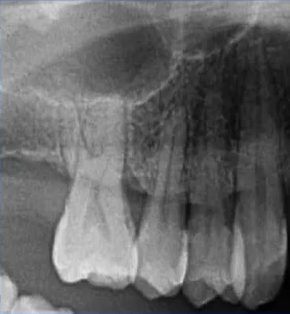

二次拍根尖片确认可看到根尖低密度炎症,临床检查与影像学检查相符,是根尖周炎。

曲面断层片怎么看口腔精读 | 一次性教你看懂曲面断层片!_https://www.jmylbn.com_新闻资讯_第21张

临床检查时发现14残根,牙龈红肿。曲面断层片上由于前磨牙转角问题,看不到残根,无法明确到底有没有残根,无法通过曲面断层片进行确诊或评估。

曲面断层片怎么看口腔精读 | 一次性教你看懂曲面断层片!_https://www.jmylbn.com_新闻资讯_第22张

这时需要加拍根尖片,很明显能看到残根。这就说明,有曲面断层片也不能排除情况。

曲面断层片怎么看口腔精读 | 一次性教你看懂曲面断层片!_https://www.jmylbn.com_新闻资讯_第23张

曲面断层片怎么看口腔精读 | 一次性教你看懂曲面断层片!_https://www.jmylbn.com_新闻资讯_第24张

临床检查45叩诊(+),牙颌面见畸形中央尖。加拍根尖片可看到,右下5根方有低密度影,并且右下5的牙根较短小,和曲面断层片上显示的大小不同,所以右下5是舌向倾斜的牙齿。